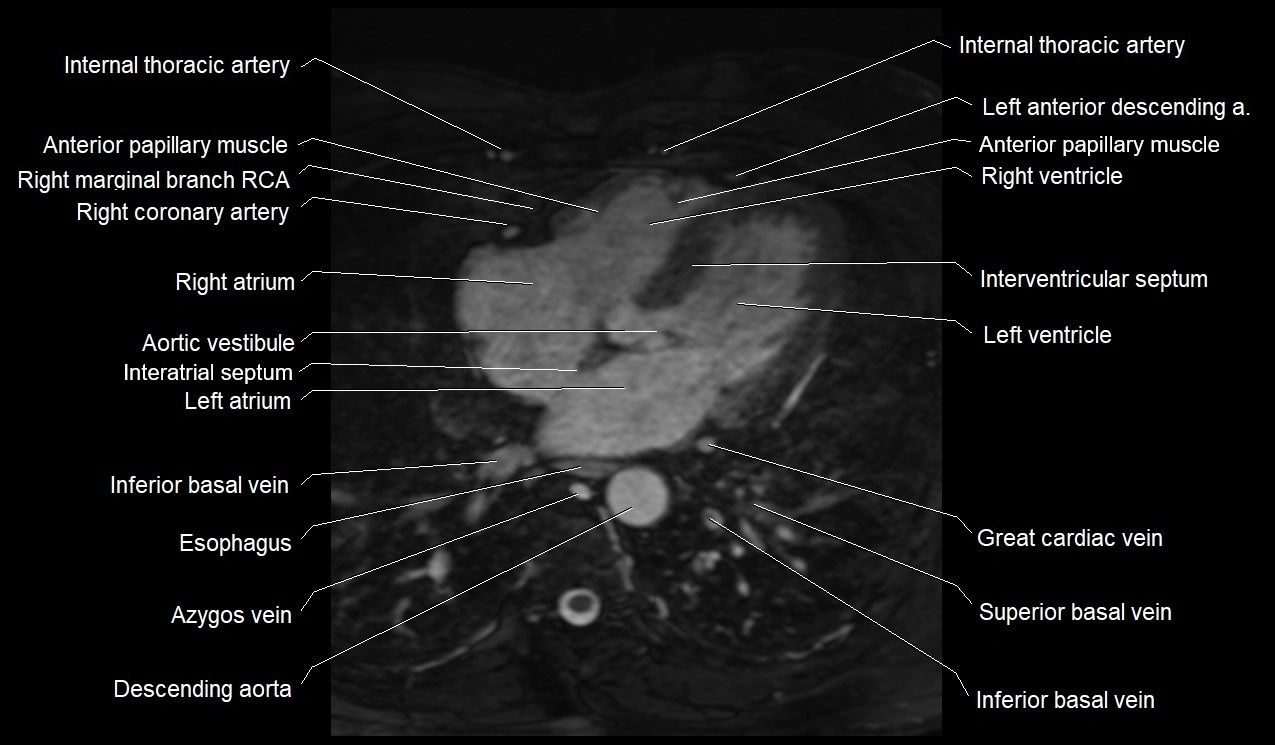

MRI image